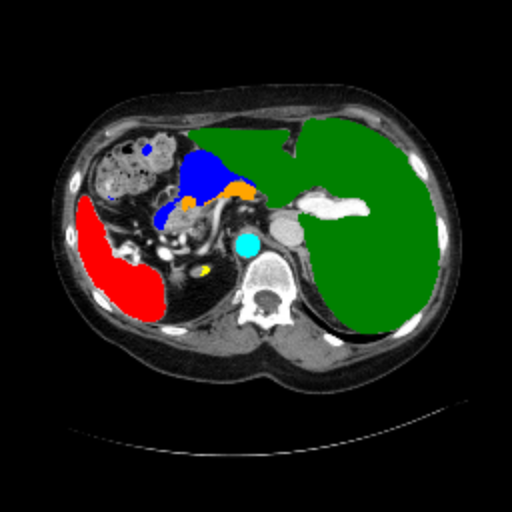

Figure 3 presents a qualitative comparison of segmentation performance on examples from the Synapse, BTCV, ACDC, and ISIC17 datasets. The first two examples (from Synapse) highlight variations in segmentation performance among U-Net, TransUnet, Mamba-Unet, and Swin-Unet. While Swin-Unet performs well in the first example, its performance decreases in the second example, particularly in segmenting the organ highlighted in blue. Additionally, it misclassifies background regions as the class highlighted in orange. In contrast, our approach demonstrates high robustness in segmenting all classes accurately and aligning well with the ground truth masks.

Across BTCV, ACDC, and ISIC17, the comparison methods exhibit varying performance depending on the task and class. For instance, Mamba-Unet struggles to segment multiple organs in BTCV, even misclassifying certain classes as others. In the ACDC dataset, both TransUnet and Mamba-Unet perform poorly in segmenting the three classes. In the last column (ISIC17), Swin-Unet oversegments the skin lesion compared to the ground truth. Unlike the comparison models, our approach consistently delivers effective segmentation across different tasks and datasets.

These qualitative findings further reinforce the quantitative results presented in the experimental section, demonstrating the effectiveness of our MambaCAFU model in handling binary and multi-class segmentation across diverse medical imaging modalities and tasks.

Slice GT Unet TransUnet Mamba-Unet Swin-UMamba MambaCAFU-V1

Figure 3: Visual comparison of segmentation examples from Synapse (first two examples), BTCV (3-4 examples), ACDC (5th example) and ISIC17 (last example). Columns: input slice, ground truth, Unet, TransUnet, Mamba-Unet, Swin-UMamba, and MambaCAFU-V1.